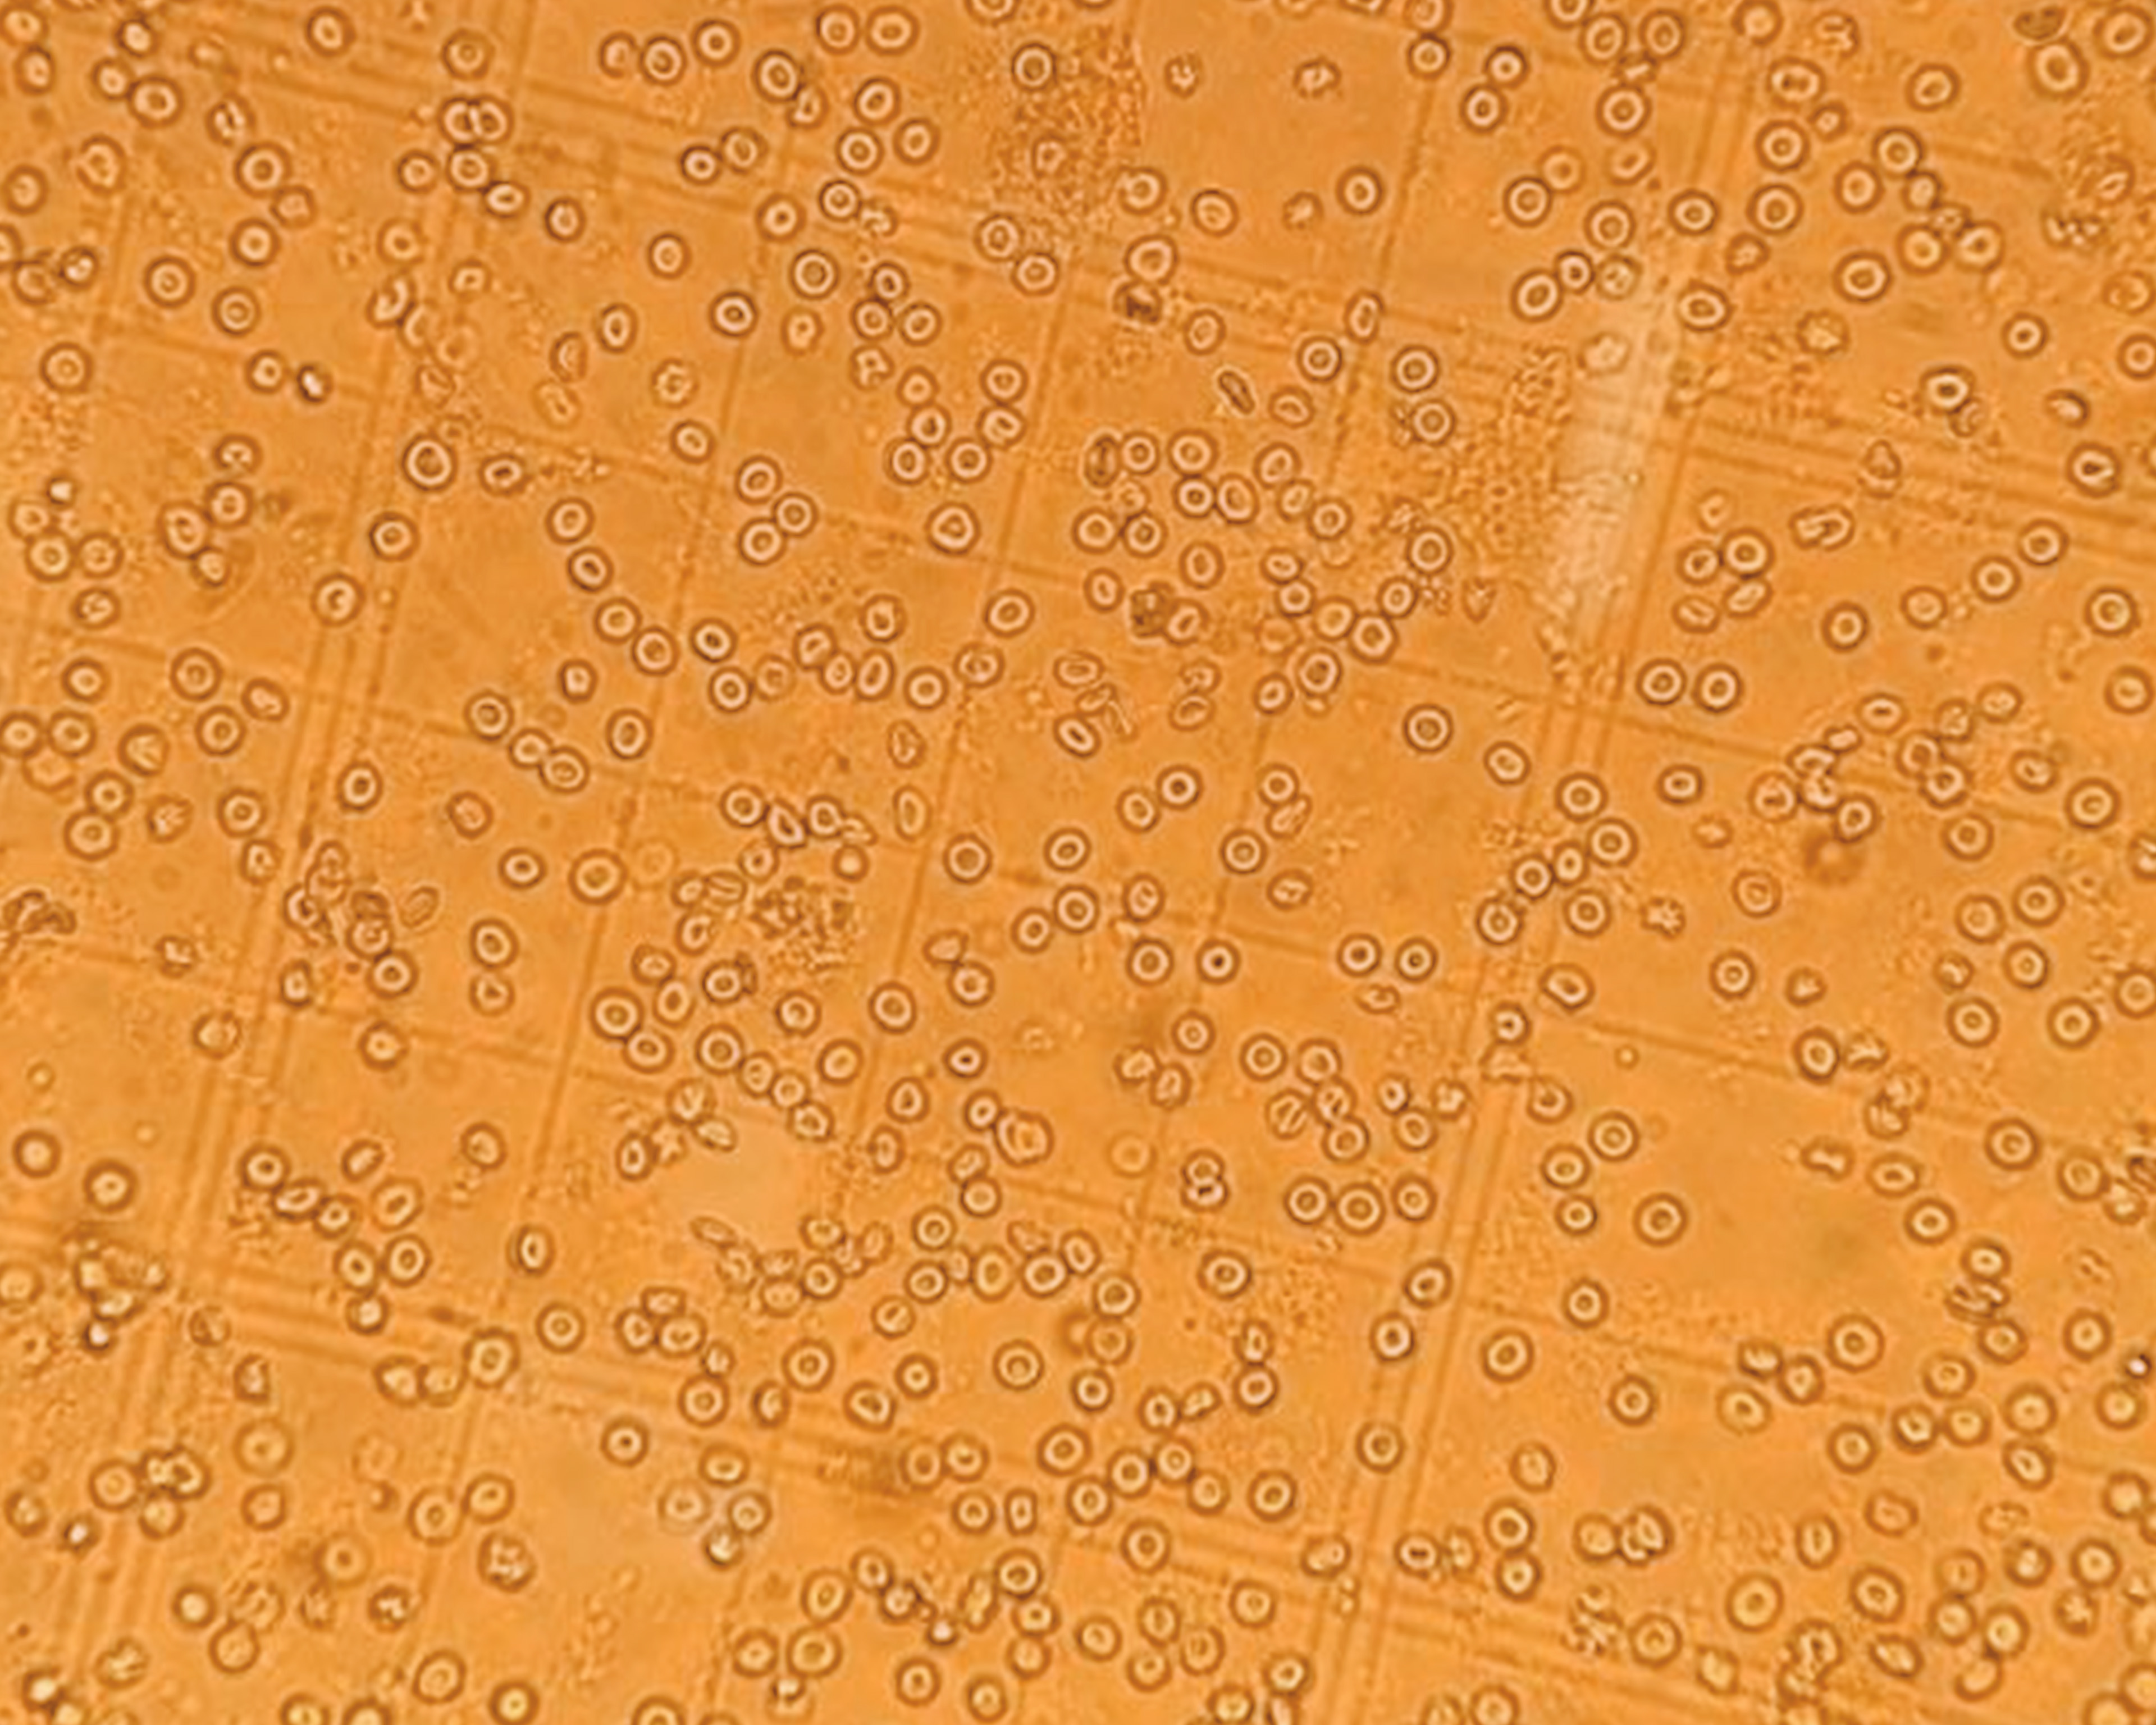

We have developed a multi-well, multi-electrode array (mwMEA) platform that enables high-throughput in vitro functional assays for modeling neurological diseases and accelerating drug screening. We established a chemically induced epilepsy models by applying traditional seizurogenic compounds with distinct mechanisms of action – picrotoxin (PTX), 4-aminopyridine (4-AP), and pentylenetetrazol (PTZ) – as well as elevated extracellular K⁺ concentrations, to rat hippocampal neurons cultured on mwMEA plates.

Increase of synchronized burst firing after treatment of various seizurogenic compounds.

The experimental setup utilized a multi-well microelectrode array (mwMEA) platform to record extracellular neuronal activities, with primary readouts including mean firing rate, burst duration, and network inter-burst interval (IBI) coefficient of variation (CV, assessing burst regularity and synchronization). Patch-clamp electrophysiology was employed to measure evoked action potentials and spike number evoked in response to current stimulation. For long-term monitoring in the genetic Dravet syndrome model, measurements encompassed mean spike frequency and spike number per burst. To test our models, we used Valproate (VPA) and Retigabine (RTG). VPA is an enhancer of GABAergic transmission and blocker of voltage-gated sodium channels. It exerts antiepileptic effects by increasing brain GABA levels, inhibiting GABA transaminase, and attenuating excitatory neurotransmission, making it effective against a broad spectrum of seizures. RTG is an activator of KCNQ channel and a modulator of GABA-A receptor. In epilepsy treatment, it reduces neuronal hyperexcitability by shifting KCNQ (Kv7) potassium channel activation to more negative potentials, increasing open channels at rest and dampening seizure propagation.

Our in mwMEA models’ validation shows increase of synchronized burst firing after treating cells with various seizurogenic compounds and the effect of Valproate at increasing concentration.